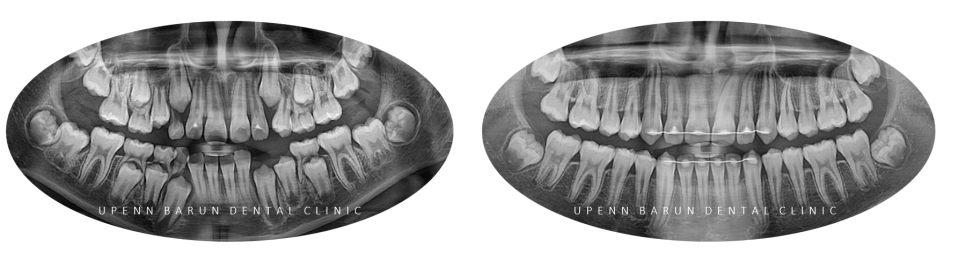

교정기간 23/2~25/1 안녕하세요. 유펜바른치과입니다. 모두 잘 지내셨나요? 오늘은 유펜바른치과 반대교합 어린이환자분의 인비절라인퍼스트 증례를 소개해 드리려고 해요 :) 교정기간 23/2~25/1 환자분의 경우 앞니에 반대교합이 있고 위아래 치아가 앞니끼리 닿고 있어 아래 앞니의 치은퇴축이 심하게 진행되고 있었는데요...

교정기간 23/2~25/1

1st Clincheck(30개)

첫번째 클린체크에는 30개의 인비절라인장치로 진행해드렸습니다.

클린체크대로

악궁이 확장되며 점차 정상적인 교합으로 변화되었습니다.

2nd Clincheck(21개)

두번째 클린체크에서는

21개의 장치로 진행해드렸는데요.

3rd(17개)

세번째는 17개의 장치로

이전의 클린체크를 이전의 클린체크를

상호 보완, 개선 하여 마무리 해드렸습니다.

4th (22개)

마지막으로 섬세한 디테일링을 위해

네번째 클린체크

(총 22개의 장치)를 진행해드렸습니다.

인비절라인퍼스트로 1차, 2차교정까지 마무리된 사진입니다 :)